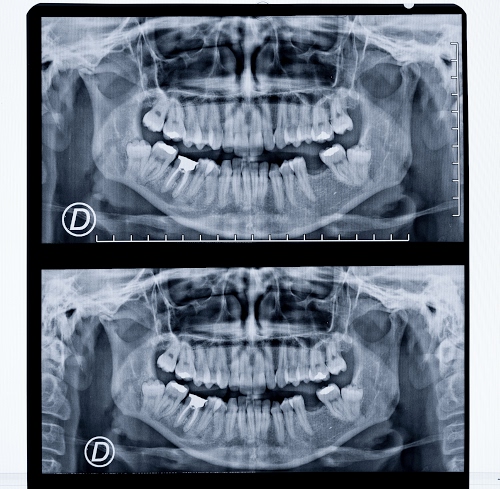

I raggi X o raggi Röntgen

di Diana Cocco - 267° nel contest raggi (galleria)

Infatti, la foto è stata realizzata da me con la D610. I colori non sono quelli di una lastra, infatti. |

Sentiamo Massimo Di Bello.    Logicamente se l'ho postata, è perché ho comunque interpretato con colore e scelta di collocamento lastra qualcosa che volevo dire; come una statua, una scultura ecc. In ogni caso "no probelm". Logicamente se l'ho postata, è perché ho comunque interpretato con colore e scelta di collocamento lastra qualcosa che volevo dire; come una statua, una scultura ecc. In ogni caso "no probelm".

@kermit: se la lastra raggi X / Röntgen (da me interpretata in taglio, colori ecc) non mi sembra un'opera bidimensionale ... o sbaglio? Se sbaglio, non vedo dove sia il problema ... Massimo di Bello la toglierà. |